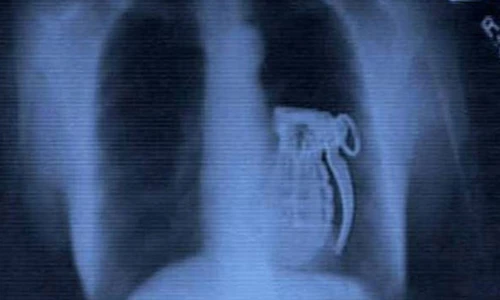

Hình ảnh khủng khiếp này thuộc về một tay khủng bố. Anh ta tìm cách nuốt chửng quả lựu đạn song không thể kích nổ nó.